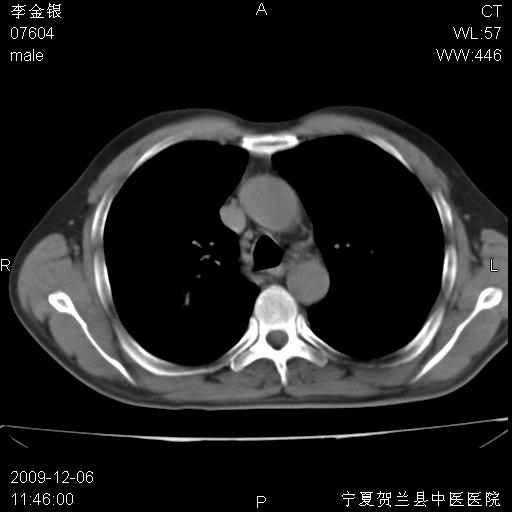

该病人 ,男,62岁,主因咳痰带血两天

考虑右肺中心型肺癌伴阻塞性肺炎及右肺门淋巴结转移,建议纤维支气管镜进一步检查。

支气管壁明显增厚 管腔狭窄,腔静脉后多个淋巴肿大,结合年龄病史考虑右肺上叶中央型肺癌并阻塞性肺炎

右肺上叶后段支气管阻塞,右上肺门占位,相应肺段阻塞性肺炎,右肺门有淋巴结肿大。诊断右肺上叶中心型肺癌,阻塞性肺肺炎、右肺门淋巴结转移。

符合中央型肺癌的ct表现并肺出血。但有一点腔静脉后有一钙化的淋巴结啊

右肺中心型肺癌伴阻塞性肺炎及右肺门与纵膈淋巴结转移很典型,可纤维支气管镜进一步检查

右侧中央型肺癌伴纵隔内淋巴结转移考虑。

考虑右侧中央型肺癌伴右肺上叶后段阻塞性炎症、肺不张、右肺门和纵隔淋巴结肿大。

右肺上叶中心型肺癌,阻塞性肺炎、右肺门和纵隔淋巴结转移。